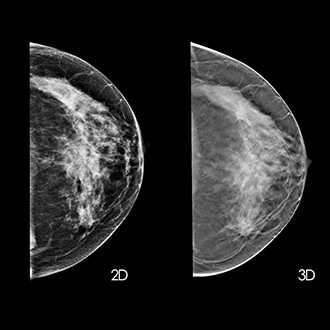

Mammography is important because in its earliest stages breast cancer may not be palpable; it may be too small to feel as a lump or tissue change. Mammography can help detect these changes two years or more before you would feel them. Physical examination is also important because premenopausal breast tissue is often dense and fibrous, which may decrease the reliability of mammography for young women.

Breast screening (mammography) is an X-ray examination of the breasts Breast screening can show breast cancer at an early stage, when they are too small for you or your doctor to see or feel

Mammography involves a tiny dose of radiation-the risk to your health from this is insignificant. The radiation dose is same as receiving dental x-ray